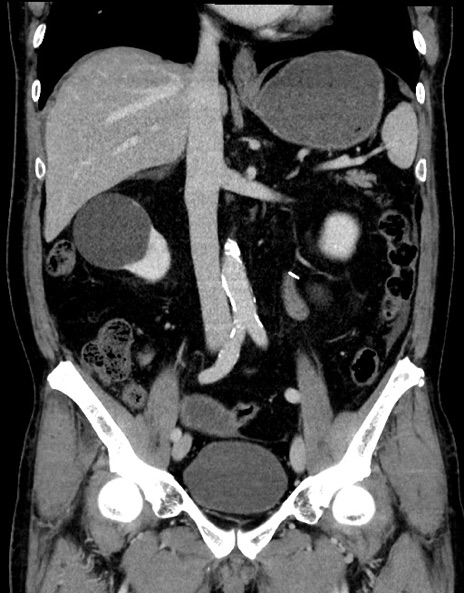

症例15(冠状断像)

【症例】70歳代男性

【主訴】腹痛

【現病歴】今朝から腹痛あり。全体的に痛い。特に左上の方。排ガスが今日はない。冷や汗が出る。

【既往歴】直腸癌術後

【身体所見】左側腹部〜上腹部に圧痛あり。腹膜刺激症状明らかなではない。軽度反跳痛。左下腹部に術後瘢痕あり。

【データ】WBC 7700、CRP 0.02